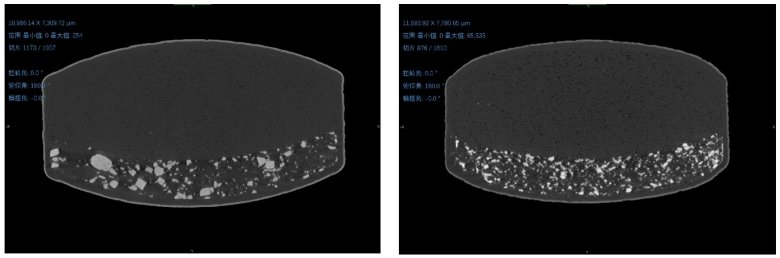

左圖為原研藥,右圖為仿制藥

左圖為原研藥,右圖為仿制藥。